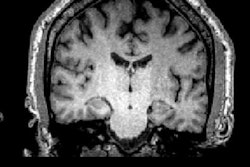

![]() |

| Left images show normal brain scans; middle and right images show scans of football players. Green and red colors demonstrate a higher level of tau protein. Scans of the players in the study reflect differing levels of tau protein and follow a pattern of progression similar to the tau deposits that have been observed at autopsy in CTE cases. Image courtesy of David Geffen School of Medicine at UCLA. |